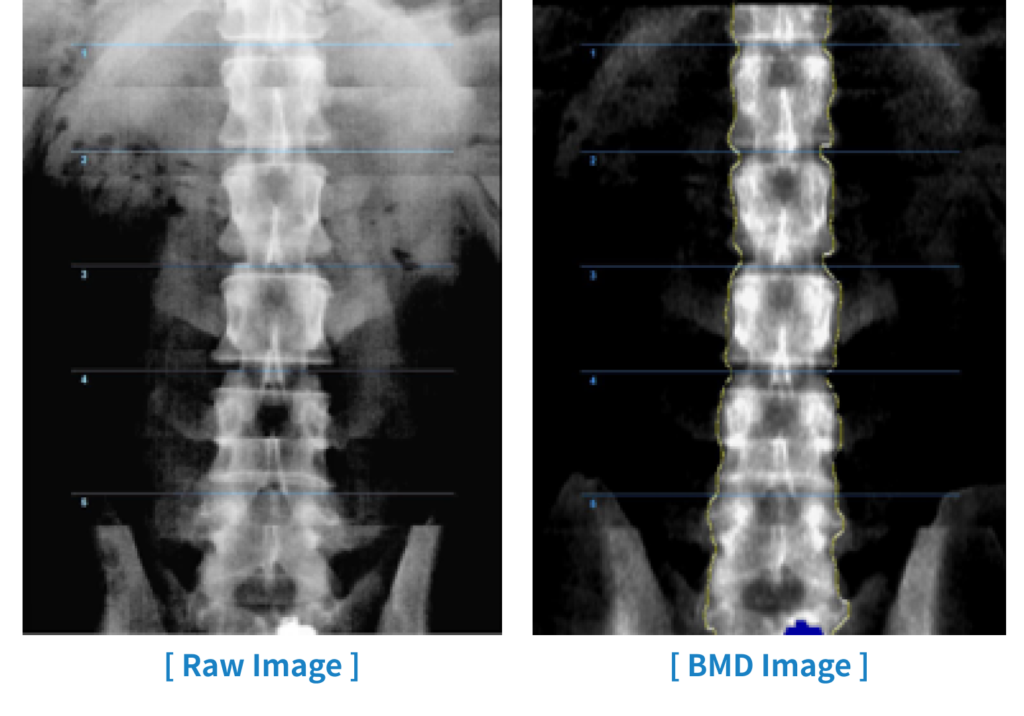

Die echte Fächerstrahltechnik mit einem 64-Kanal-Linear-Array-Detektor ermöglicht eine schnelle Messung innerhalb von 30 Sekunden mit hochauflösenden Bildern. Auf dieser Grundlage erhöhen die bereitgestellten Rohbilder nicht nur den Komfort bei der ROI-Einstellung, sondern sind auch eine große Hilfe bei der Ableitung genauer Diagnoseergebnisse.

Rohbilder

Durch die Bereitstellung von Rohbildern werden die Genauigkeit und Reproduzierbarkeit der Ergebnisse der Knochendichtediagnose verbessert.